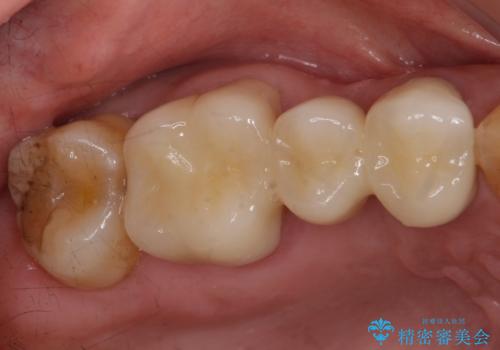

- 他院でブリッジの仮歯を入れたが、外れやすいため転院を希望された患者様です。

支台歯の形が角度が大きくついた形に形成してあり、外れやすい形になっていたため修正してから歯型をとりました。

- 36.3万円(ジルコニアクラウン10万円x3本)費用は治療当時の料金となります

根の治療のやり直しは特に行っていません。